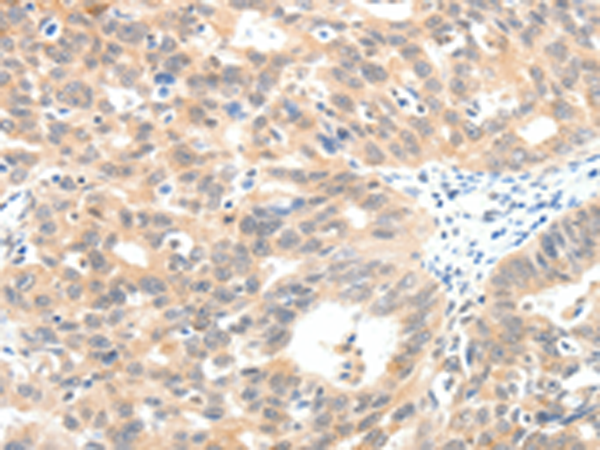

IHC positive control: |

Human ovarian cancer |

IHC Recommend dilution: |

25-100 |